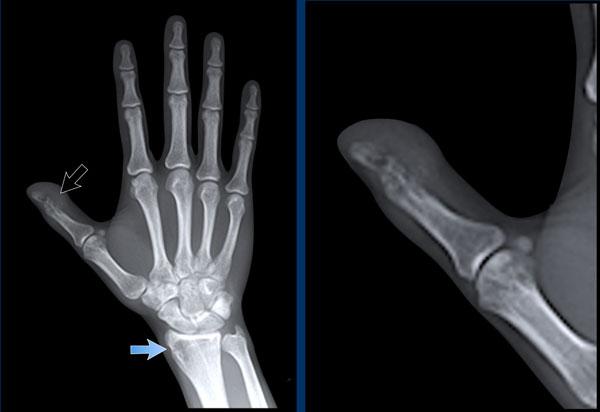

Hình ảnh bào mòn xương vùng rìa điển hình và hẹp khe khớp tại các khớp MCP 3-5.

Lưu ý hình ảnh hẹp khe khớp đồng đều tại các khớp MCP.

Các khớp liên đốt gần (PIP) chỉ biểu hiện hẹp khe khớp tối thiểu.

Đây là trường hợp viêm khớp dạng thấp giai đoạn cuối với các thay đổi bào mòn nặng nề và đứt dây chằng gây trật khớp tại các khớp MCP.

Phân ly xương thuyền – xương nguyệt (mũi tên trắng) là dấu hiệu thường gặp do tình trạng viêm lan tỏa khối xương cổ tay. Cả tình trạng phân ly lẫn viêm đều có thể gây hẹp khe khớp quay – cổ tay.

Lưu ý hình ảnh bào mòn xương đầu dưới xương trụ kèm theo sưng nề phần mềm xung quanh (mũi tên xanh).